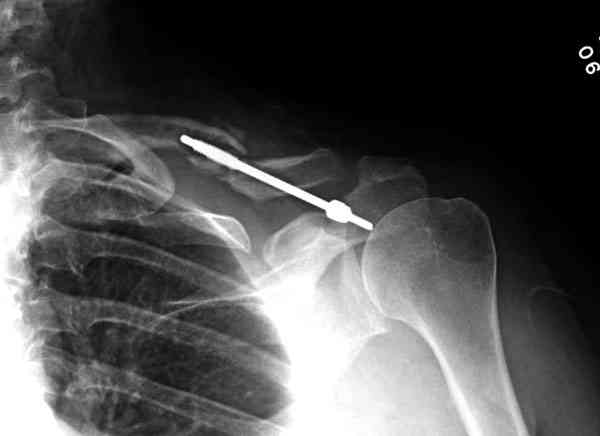

Консервативное лечение, через 8 мес. операция Rockwood pin с костной пластикой в нашем городе другим врачом. После 8 недели падение, гвоздь удален оперирующим хирургом, больная направлена к нам. Фиксация реконструктивной пластиной с трикортикальным графтом, добавлен BMP-2. Для стабилизации фиксацию провели через акромион.

Вот уже два месяца больная также продолжает жаловаться на боли, буквально на днях удалили акромиальную часть пластины с специальной пилой с алмазным покрытием для медицинского металла. До сих пор судьба ложного сустава неизвестна....